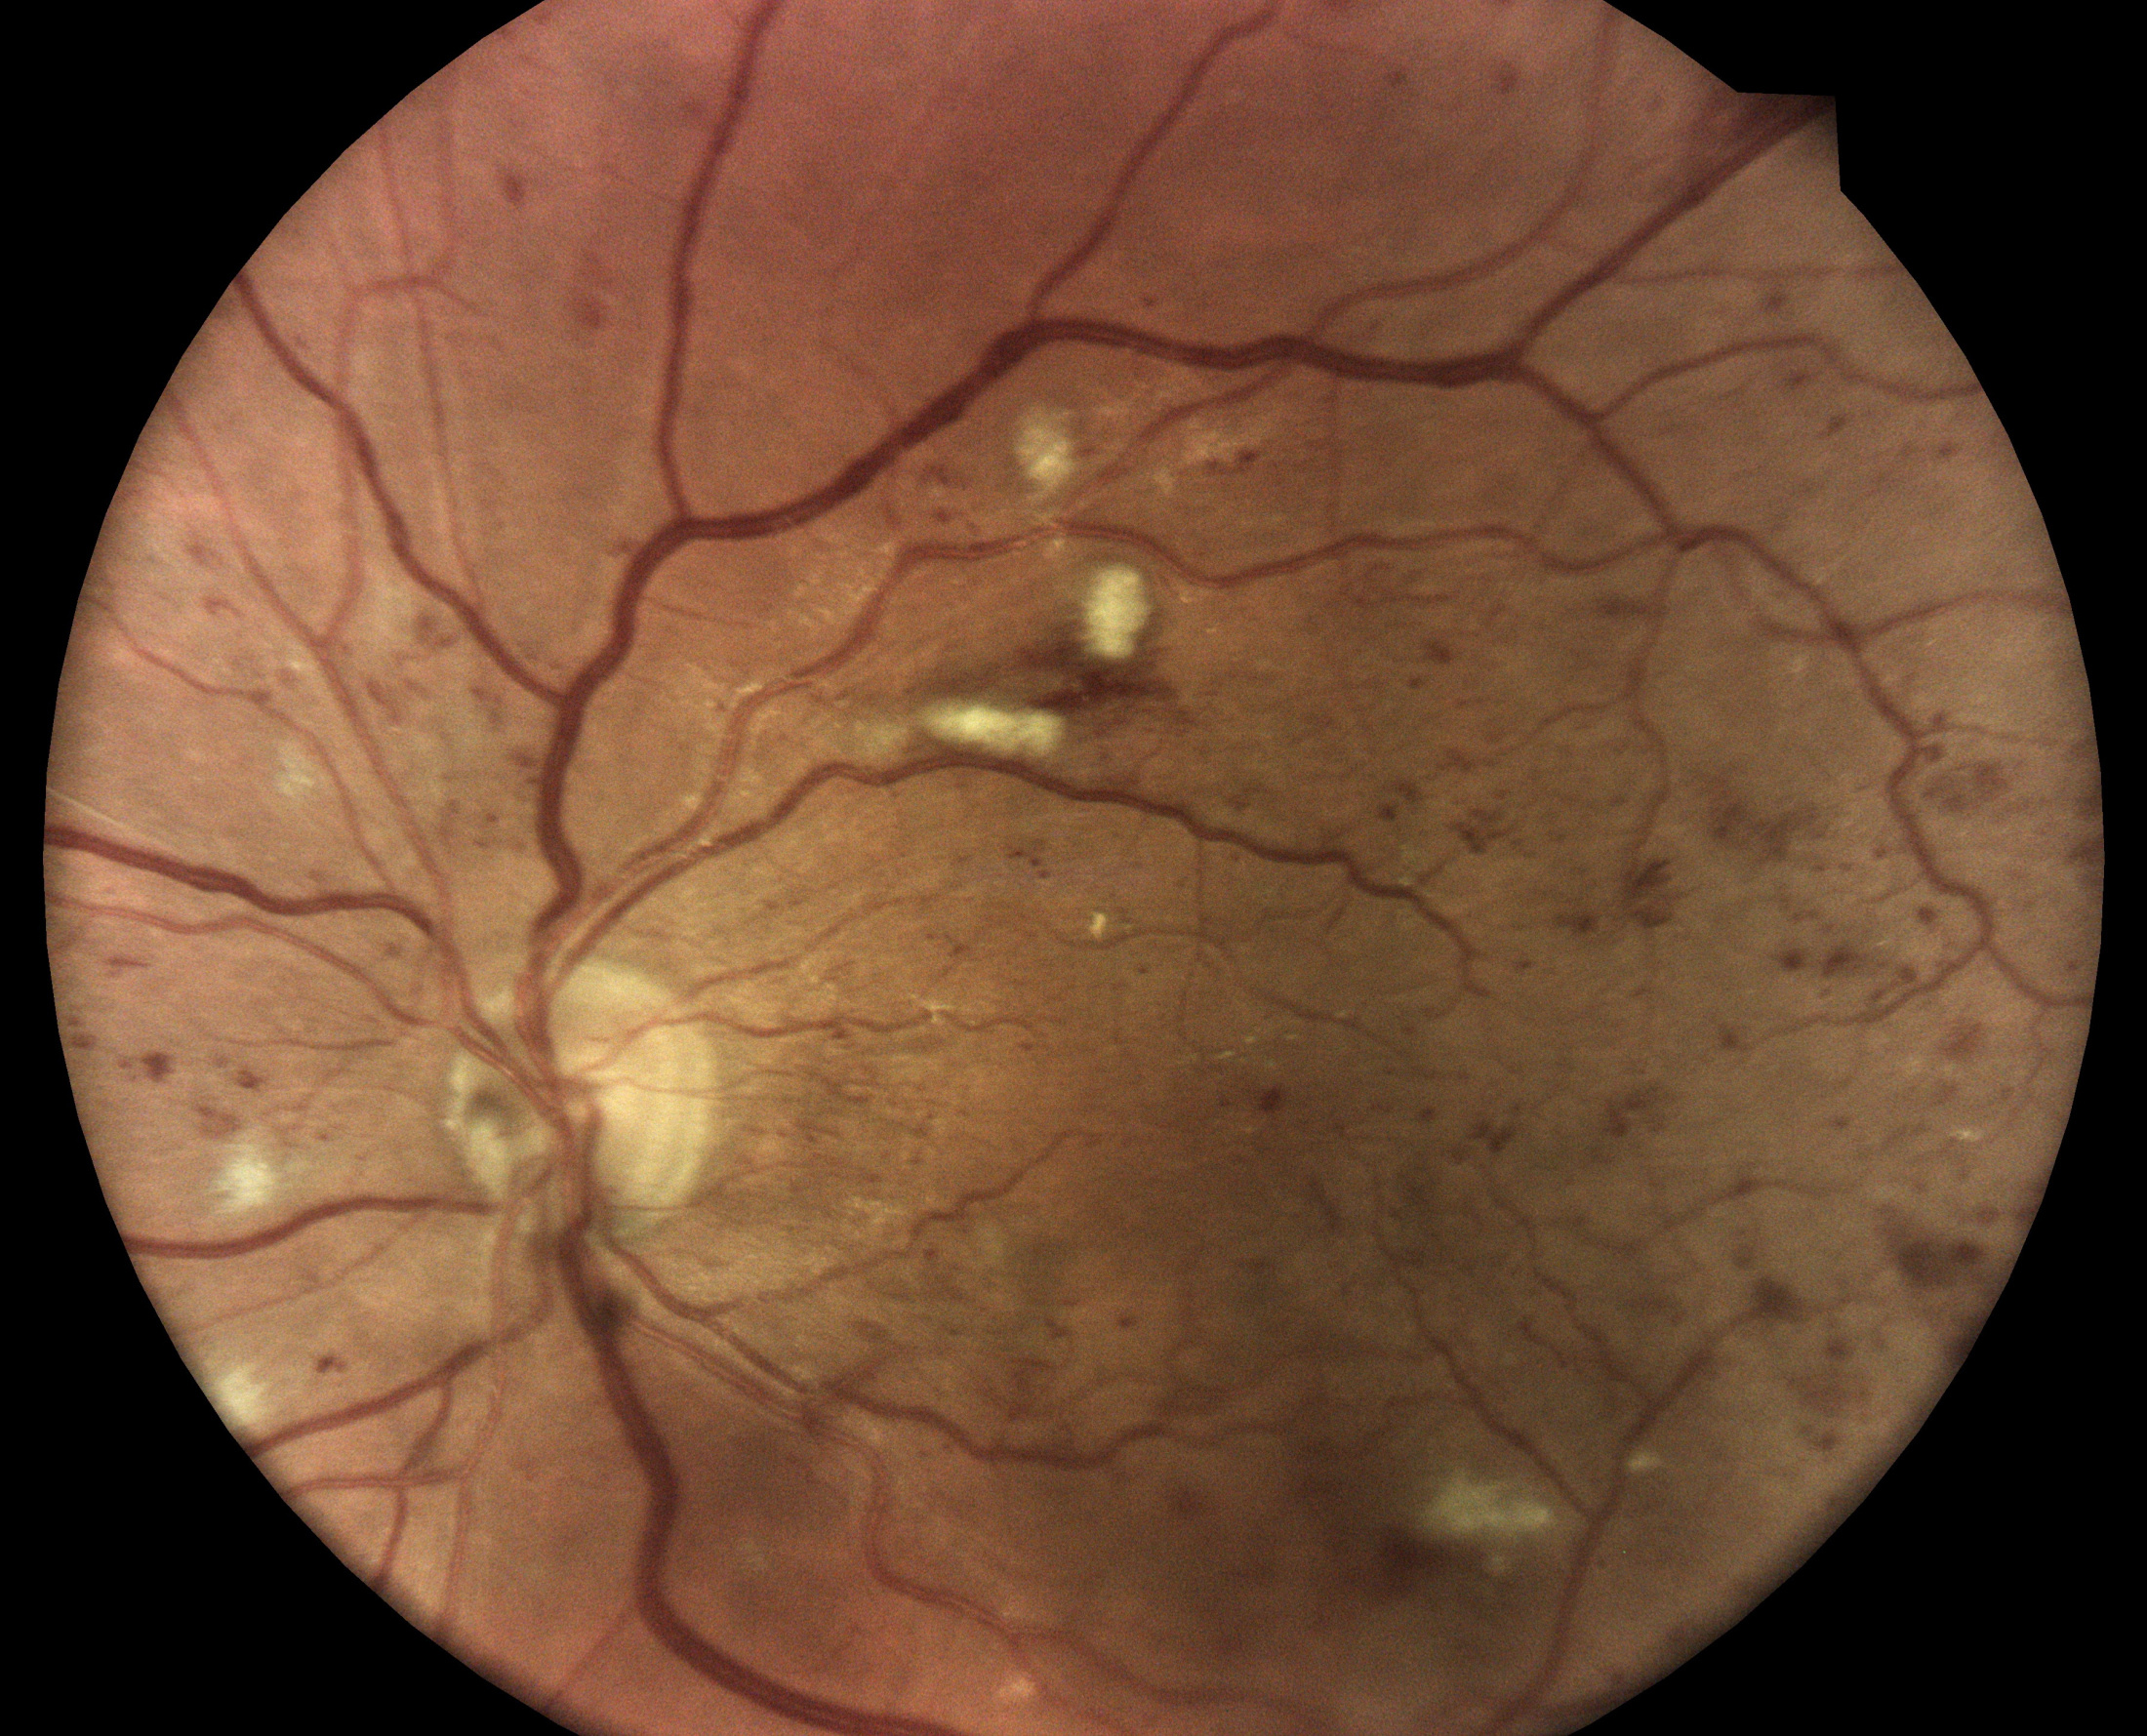

Diabetická retinopatia

Diabetická retinopatia je hlavnou príčinou straty zraku u dospelých vo veku medzi 20 - 74 rokov. Viac ako jedna tretina z odhadovaných 285 mil. ľudí s cukrovkou na celom svete vykazuje príznaky diabetickej retinopatie. Diabetická retinopatia je na vzostupe v dôsledku zvyšujúcej sa prevalancie cukrovky, stárnutia populácie a predlžujúcej sa dĺžky života ľudí s cukrovkou.

Fundus kamera iCare DRSplus urobí celkovo 4 vysoko kvalitné snímky (dve z pravého a dve z ľavého oka), ktoré sa automaticky ukladajú na cloud a posielajú sa na spracovanie AI - umelej inteligencii. Report je dostupný ihneď a ten je možné prekonzultovať s pacientom počas tej istej návštevy u lekára.

Kamera iCare DRSplus spoločne pomocou softwaru využívajúceho umelú inteligenciu iCare RETCAD® vykonáva vyhodnotenie skríningu diabetickej retinopatie, ktorá šetrí váš drahocenný čas, umožňuje včasnú intervenciu a pomáha poskytnúť včasnú zdravotnú starostlivosť. Anlýza pomocou iCare RETCAD® nenahradzuje vyšetrenie zdravotného stavu očí.

- infračervené mapy zvýrazňujúce svetlé a červené lézie/poškodenia